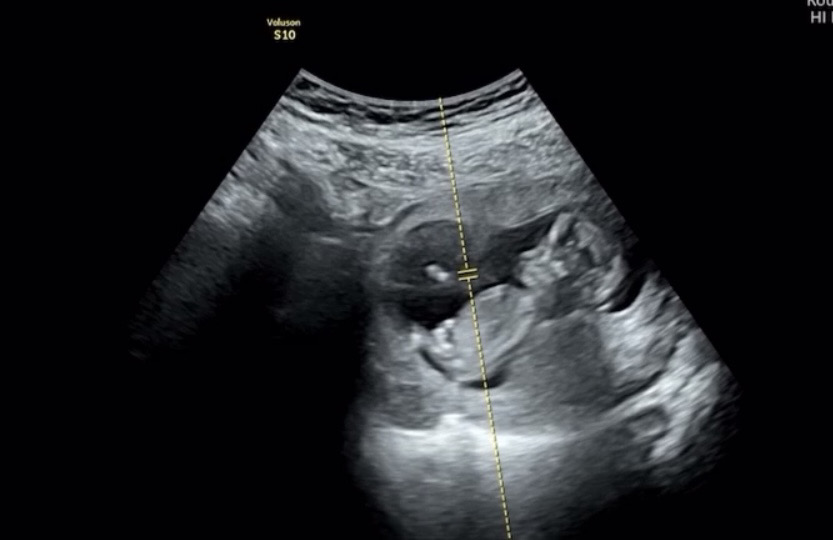

고수님들 저도 투표해주세요 💕12주 촘파입니다

뱃살 때문에 희미하게 보이신다고 ;;; ㅠㅠ ㅋㅋ 투표 마구마구 해주세용